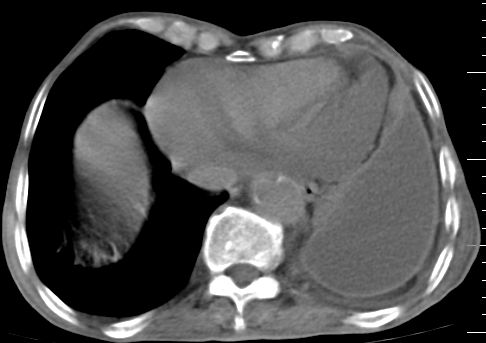

标题: CT10141:男、84岁,咳嗽、咯血1年。 [打印本页]

标题: CT10141:男、84岁,咳嗽、咯血1年。

支持左侧中央型肺癌伴下叶肺不张\\纵隔淋巴结转移.左侧包裹性胸腔积液\\心包积液.左侧少量胸腔积液..慢性支气管炎伴部分间质纤维化.

支持:左侧中央型肺癌伴下叶肺不张\\纵隔淋巴结转移.左侧包裹性胸腔积液\\心包积液.左侧少量胸腔积液..慢性支气管炎伴部分间质纤维化.另:支气管分支根部明显阻塞 狭窄,内膜凸凹不平,提示内膜增生物。

咯血病史较长,左肺下叶实变,体积未明显缩小,隐约可见血管影及坏死阴影,双肺门及纵隔淋巴结增大,心包增厚积液,纵隔右移位,单侧胸腔积液,首先考虑:大叶型肺泡癌伴纵隔心包转移。